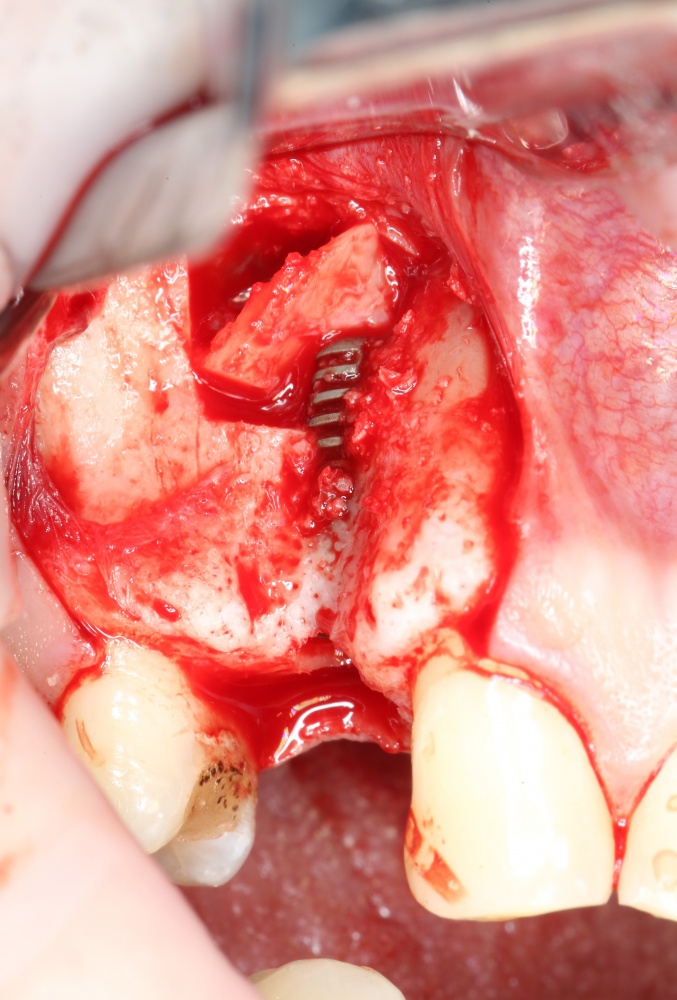

Простой. Надежный. Дешевый. Способ остеопластики.